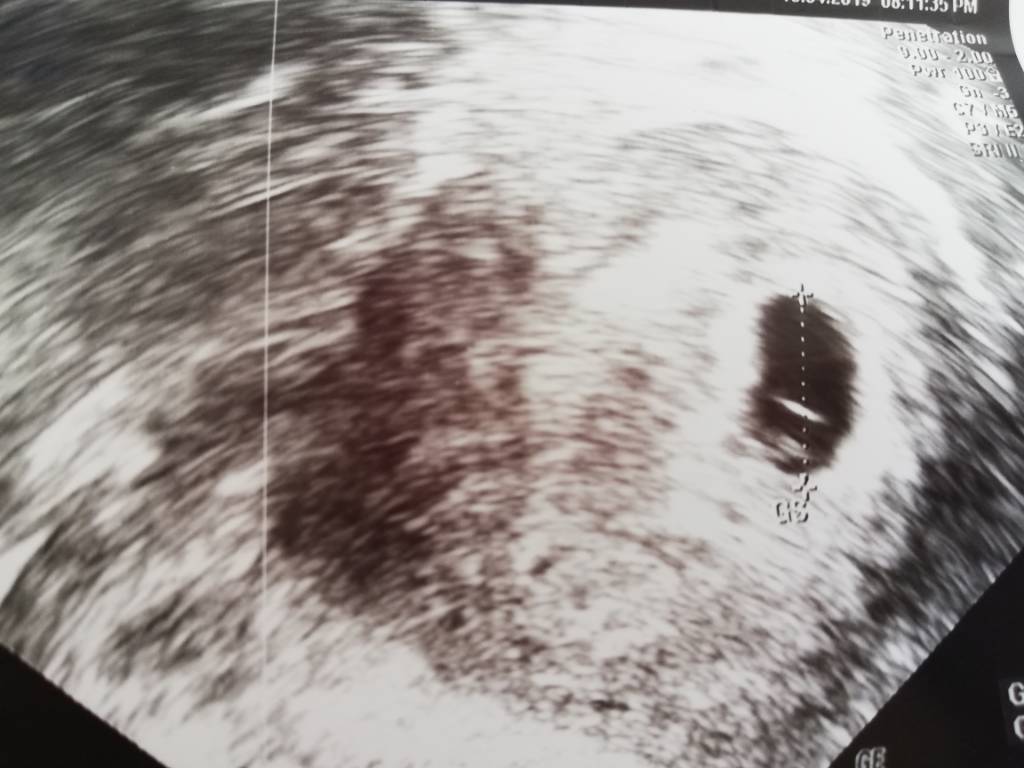

Cześć dziewczynki. Obserwuję Was od jakiegoś czasu, wczoraj byłam na badaniu i ciąża została potwierdzona, więc postanowiłam do Was dołączyć. Termin mam na 10 grudnia, obecnie jestem w siódmym tygodniu ciąży (6t 3d). Dołączam zdjęcie bo z tego co czytałam niektóre dziewczyny bardzo lubią oglądać fotki testów lub usg [emoji39] Serduszko już było słychać [emoji3526]

Mam 34 lata, to moja druga ciąża, z pierwszej mam prawie 9-letniego synaZobacz załącznik 963322